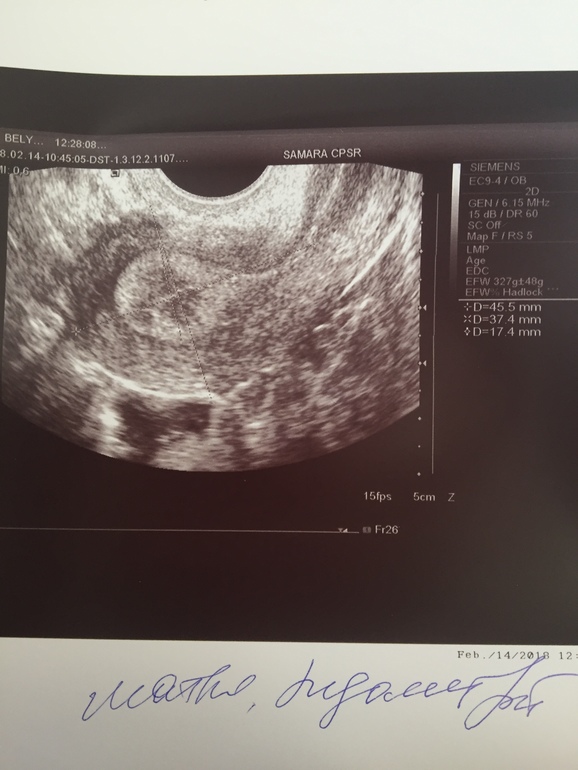

Эндометрий 17 мм на 16 дц

Вчера был 16 дц мы вот вот только прилетели с отпуска и я сразу побежала к репродуктологу.я попросила сделать УЗИ, Посмотреть овуляцию... и тут я ни как не ожидала такого результата.

Легла, узистка начала смотреть и сразу говорит, ты вроде беременна!!!! Мои слова, я конечно буду очень рада, но наверно это невозможно... я тут по-поводу бесплодия... она говорит у тебя эндометрий островат, это возможность беременности, купи сегодня дорогой тест и сделай!!! На что я ответила, что сомневаюсь, что на 16 дц тест что то покажет. Про себя думаю, блин может смена климата, отдых и правда что то изменил.... ну тут мои мысли отпали, так как она начала говорить, что скорее всего овуляции небыло... в левом яичнике лоцируется пониженной эхогенности округлое образование тонкой капсулой диаметром 11,5 мм. Эндомерий толщиной аж 17,4 мм!!!!!!!! Заключение: эхо-признаки гиперплазии эндометрий. Эндометриома левого яичника. Я следом пошла обратно к врачу, показала ей УЗИ, она меня ждала.... говорит, что беременности не будем исключать, но эндометрий на 16 дц очень большой, обозначила что фолликул много - это хорошо при моем АМГ!

Фото УЗИ ниже